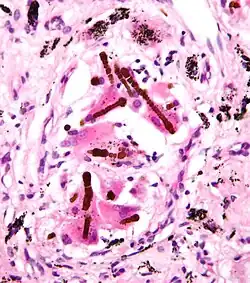

_by_core_needle_biopsy.jpg)

No carcinoma de pulmão pequenas células (CPC), as células contêm densos grânulos neurossecretores (vesículas contendo hormônios neuroendócrinos), que conferem a esse tumor uma associação com a síndrome endócrina/paraneoplásica.[55] A maior parte dos casos surge nas grandes vias aéreas (brônquios primários e secundários).[9] Esses tumores crescem rapidamente e se espalham precocemente no curso da doença. 60–70% dos pacientes já possuem doença metastática à apresentação. Esse tipo de câncer de pulmão está fortemente associado ao tabagismo.[7]